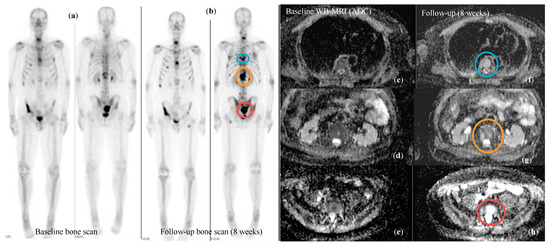

3.5. Response Assessment in Metastatic Prostate Cancer

| Padhani et al Eur Urol 2017 (MET-RADs-P) * [10] | WB-MRI |

|